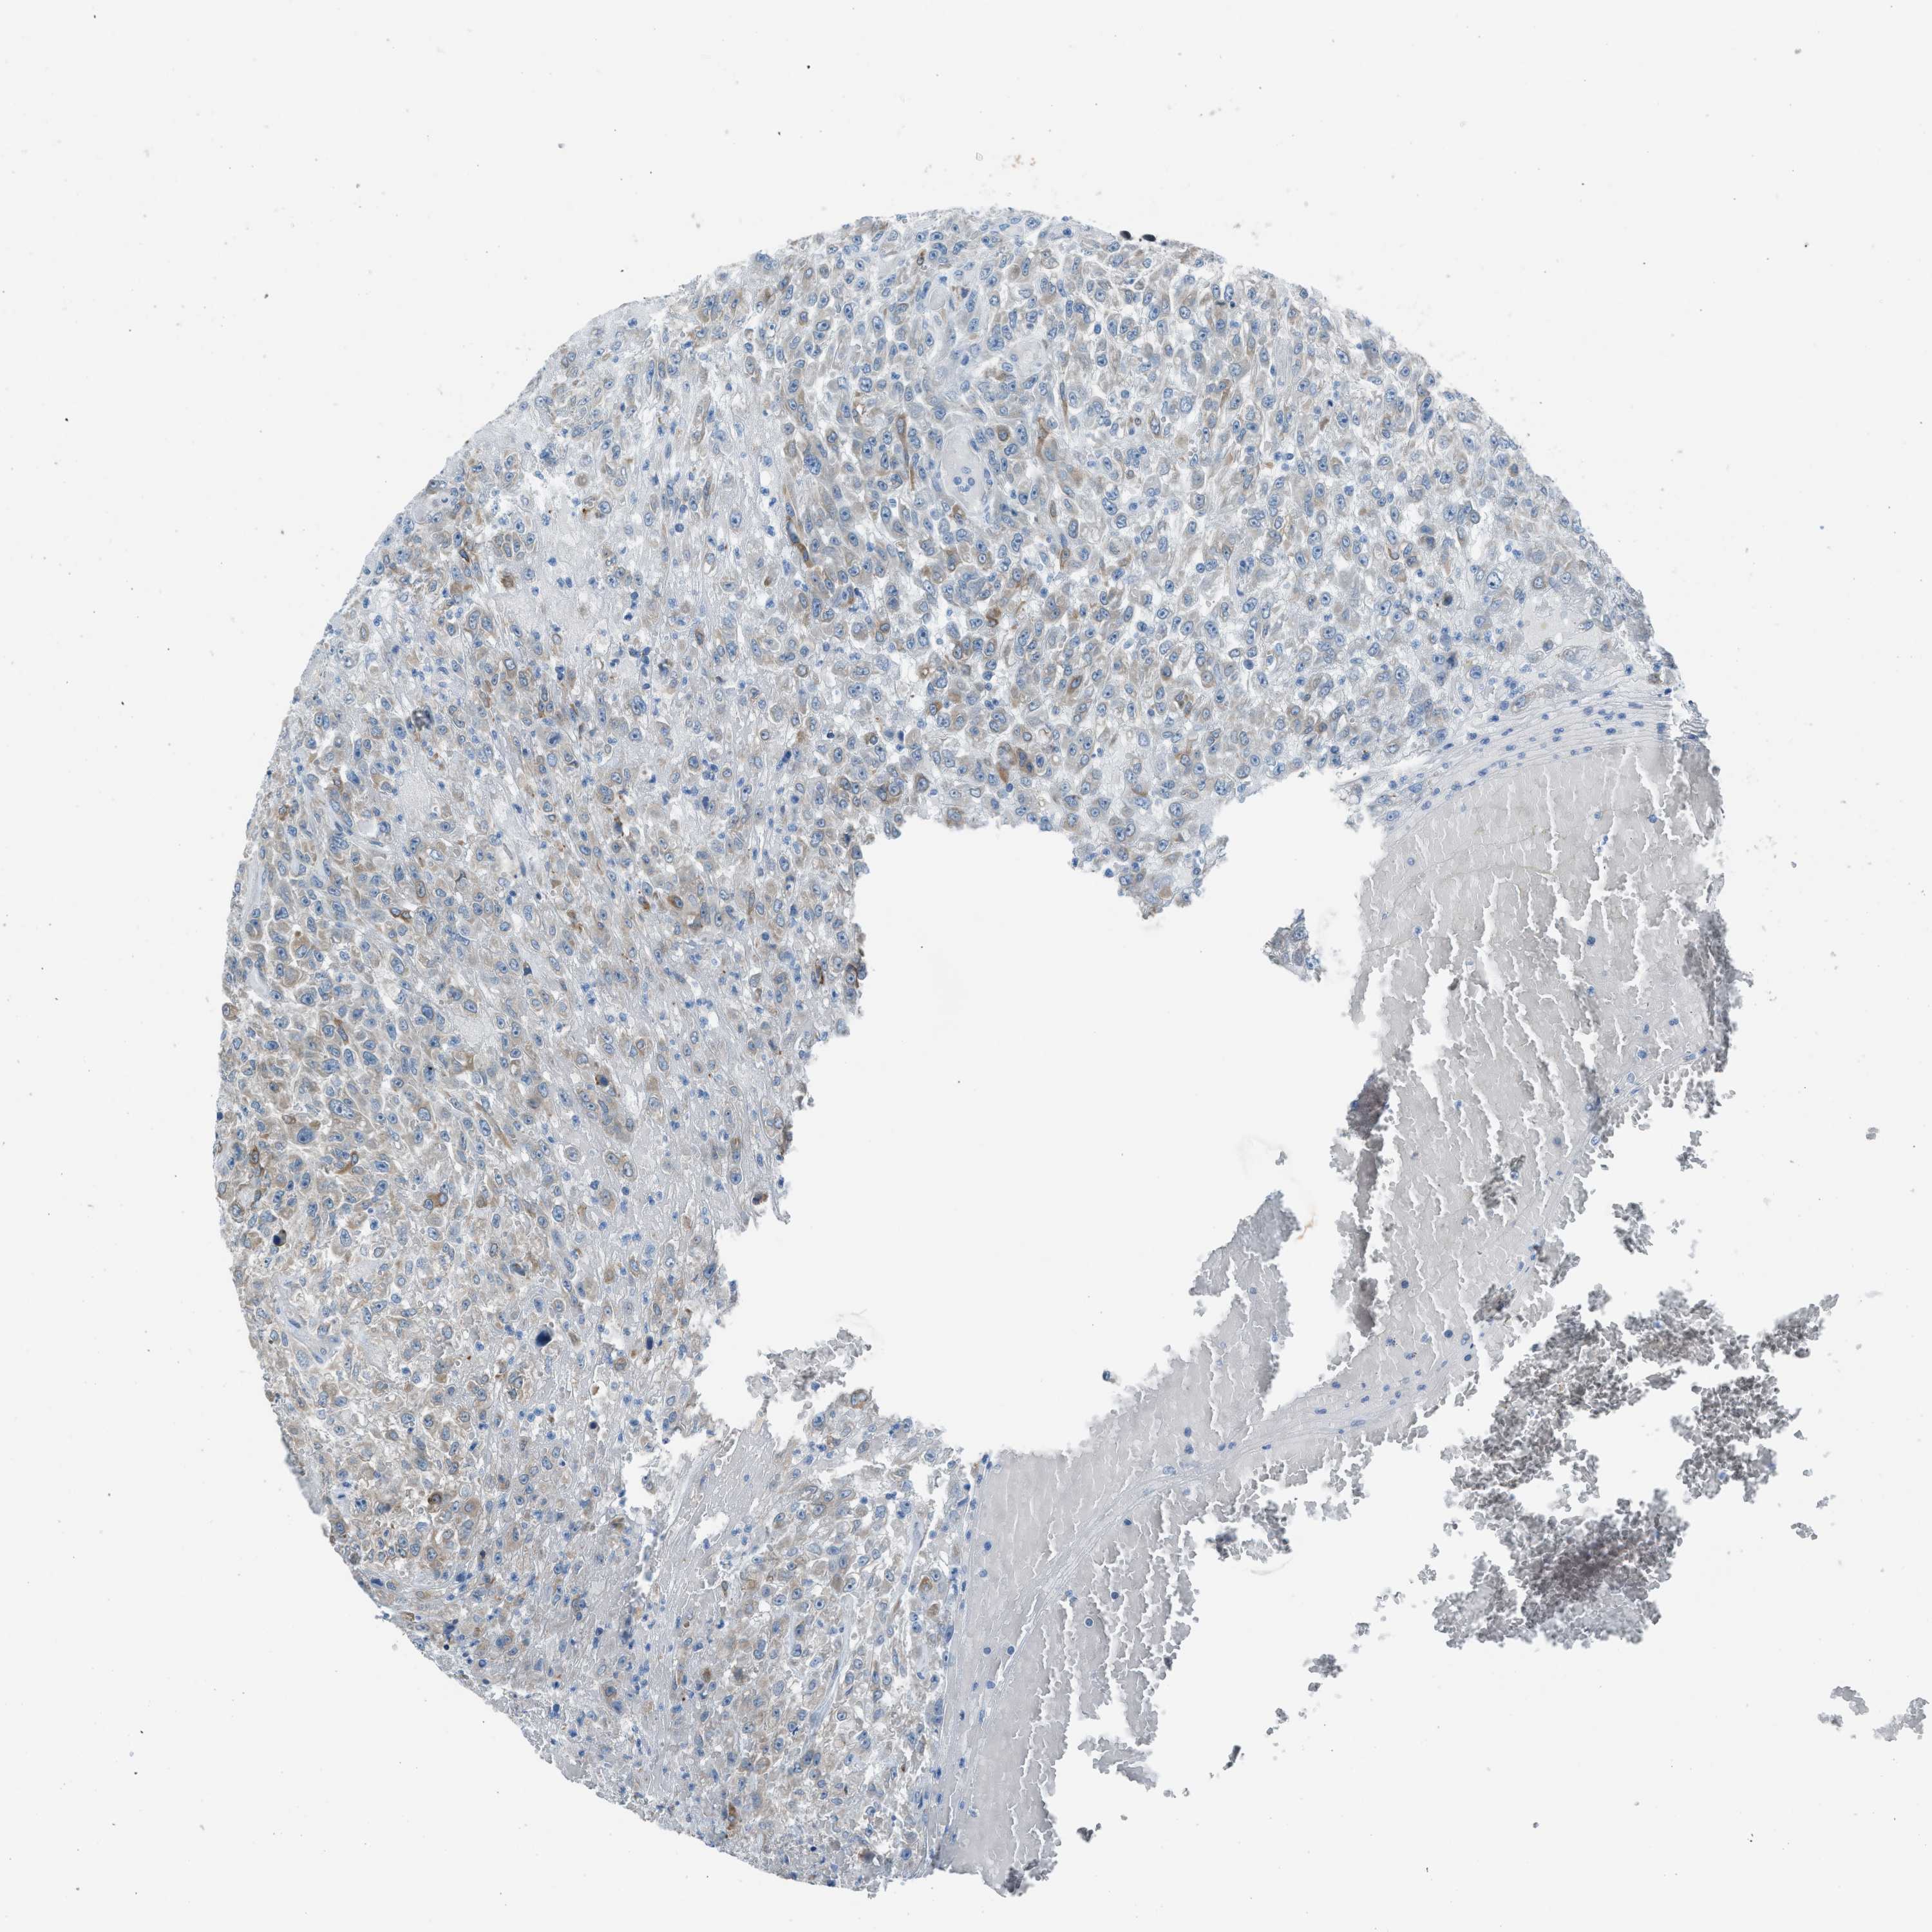

UROTHELIAL CANCER - Protein expressioni

A mouse-over function shows sample information and annotation data. Click on an image to view it in a full screen mode. Samples can be filtered based on level of antibody staining by selecting one or several of the following categories: high, medium, low and not detected. The assay and annotation is described here.

Note that samples used for immunohistochemistry by the Human Protein Atlas do not correspond to samples in the TCGA dataset.

Antibody stainingi

Antibody staining in the annotated cell types in the current human tissue is reported as not detected, low, medium, or high, based on conventional immunohistochemistry profiling in selected tissues. This score is based on the combination of the staining intensity and fraction of stained cells.

Each image is clickable and will lead to virtual microscopy that enables deeper exploration of all samples and also displays staining intensity scores, fraction scores and subcellular localization as well as patient and tissue information for each sample.

Antibody HPA016812

Staining

High

Medium

Low

Not detected

Intensity

Strong

Moderate

Weak

Negative

Quantity

>75%

75%-25%

<25%

None

Location

Nuclear

Cytoplasmic/membranous

Cytoplasmic/membranous,nuclear

Urothelial carcinoma, Low grade

Urothelial carcinoma, High grade